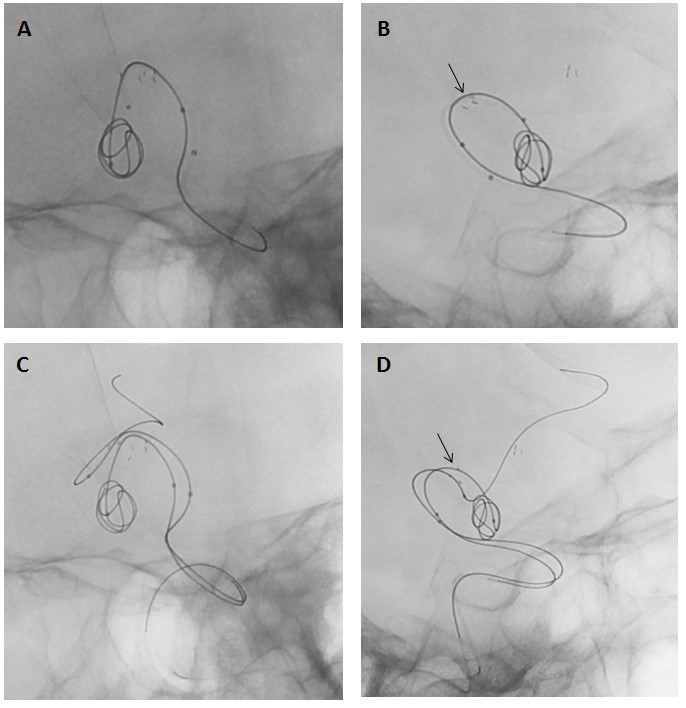

Imagen 3: Capturas de fluoroscopia sustraída (A y B) y sus correspondencia en reconstrucción 3D (C y D respectivamente) que muestran la proyección desde la que se procede a liberar el stent en segmento A2 de la ACA izquierda. Se pueden apreciar la posición de las dos marcas del microcatéter de liberación de stent (flechas finas largas), las dos marcas del stent (flechas huecas) y las marcas del microcatéter de embolización (cabezas de flecha) con coil largo parcialmente desplegado en el saco aneurismático. En la imagen E se observa el inicio de la liberación del stent con las patillas distales abiertas (flechas huecas).

A continuación, se procede a microcateterizar el segmento A2 de la ACA izquierda con microcatéter Excelsior SL-10 alcanzando posición desde donde se desplegará stent Neuroform Atlas. Previamente al despliegue del mismo, se microcateteriza el saco aneurismático con un segundo Excelsior SL-10 y se introduce parcialmente un primer coil largo de 7mm x 14 cm que ayudará a mantener la posición de embolización mientras se procede a la liberación del stent (imagen 3).